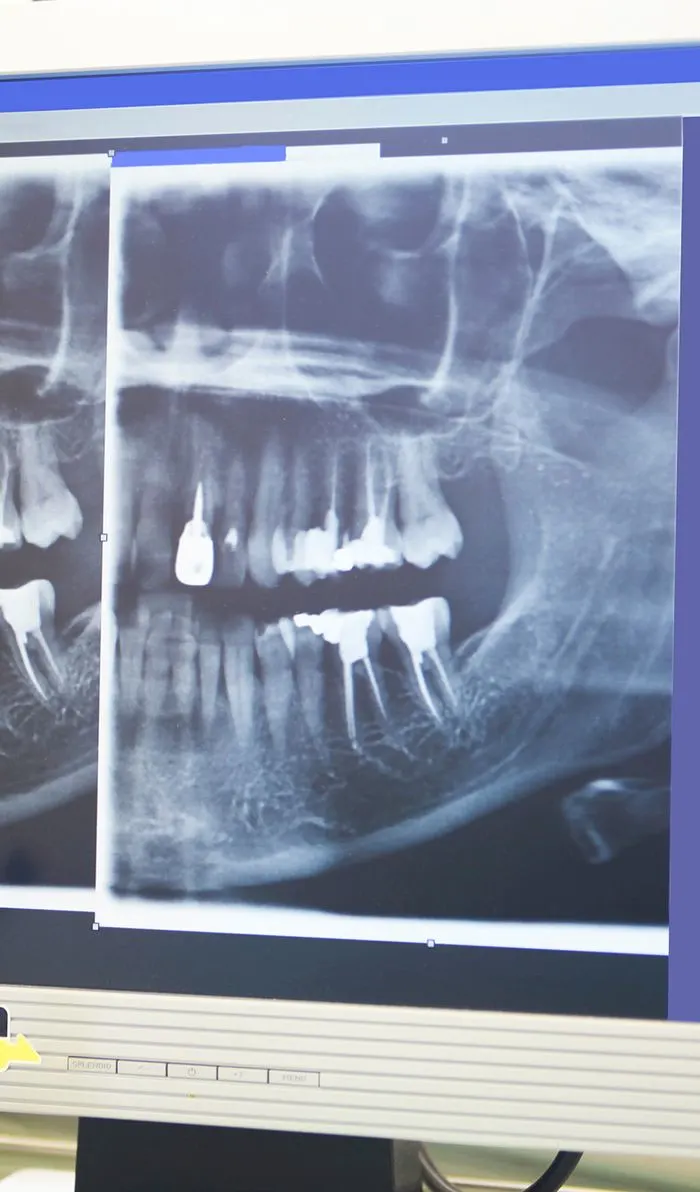

Your dentist will begin with a comprehensive examination of your tooth and x-rays to identify the cause of your dental discomfort. If an infection is present, they'll assess its severity to determine if a root canal is the appropriate treatment option.If root canal therapy is necessary, your dentist will ensure the treatment area is completely numb, including the nerves. Before starting the procedure, they'll discuss various sedation options with you to ensure your comfort throughout the treatment.